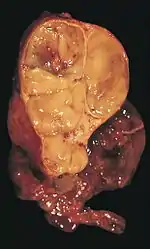

Anatomie pathologique

Classification histologique

Grands types de thymomes

Les thymomes se développent à partir des cellules épithéliales thymiques, d'où leur nom global de « tumeurs épithéliales thymiques ». Les tumeurs de la loge thymique développées à partir d'autres types de cellules ne sont pas des thymomes. Ainsi, les lymphomes atteignant le thymus ne doivent pas être considérés comme appartenant aux thymomes, de même que les tumeurs localisées dans le médiastin antérieur et développées à partir de cellules non natives du thymus (tumeur fibreuse solitaire, lipome, liposarcome, tumeurs germinales...)[45].

Histologie

La classification histologique de l'OMS identifie les thymomes selon la forme des cellules malades, réparties en type A (ovalaires ou en fuseau) et en type B (dendritiques ou épithélioïdes). Les différents types B sont différenciés par la proportion de thymocytes et de cellules atypiques par rapport à la quantité de lymphocytes ; les types B1 sont plus riches en lymphocytes et les types B3 en sont plus pauvres. Les thymomes comportant à la fois des caractéristiques de type A et de type B1 sont dits de type AB[31],[46]. Les carcinomes thymiques, eux, présentent les caractéristiques histologiques générales des carcinomes[46].